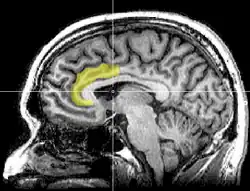

Dans une étude utilisant l'imagerie cérébrale (IRM fonctionnel) et publiée dans la revue Science en 2003, Naomi Einsenberger et ses collaborateurs ont montré que le sentiment d'exclusion sociale, crée artificiellement pendant l'expérience, activait des zones du cerveau similaires à celles activées lorsque l'individu éprouve une douleur physique[16],[17]. Leurs recherches sur ce problème ont continué à indiquer l'implication du cortex cingulaire antérieur dans la douleur (ou souffrance) engendrée par le rejet des pairs ou d'autres conditions d'exclusion sociale contrôlées expérimentalement[18]. Ces résultats sont discutés par les spécialistes en neurosciences sociales et leur interprétation n'est pas consensuelle[19].